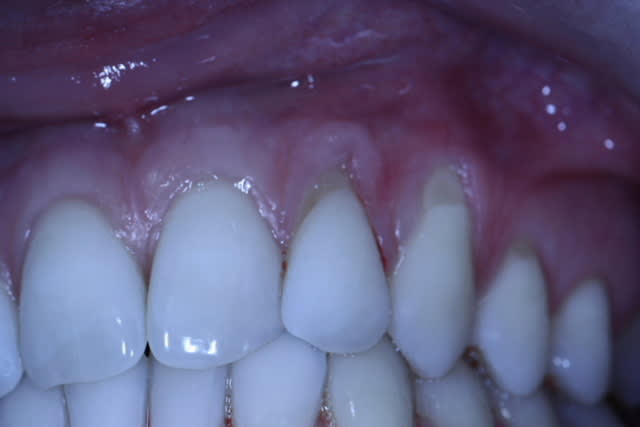

J'hésite sur le choix de la technique.

La patiente est jeune, non fumeuse, aucun problème de santé et très préoccupée par son problème de gencive.

En clair très motivée.

Les récessions sont des Cl I de Miller, donc bon pronostic.